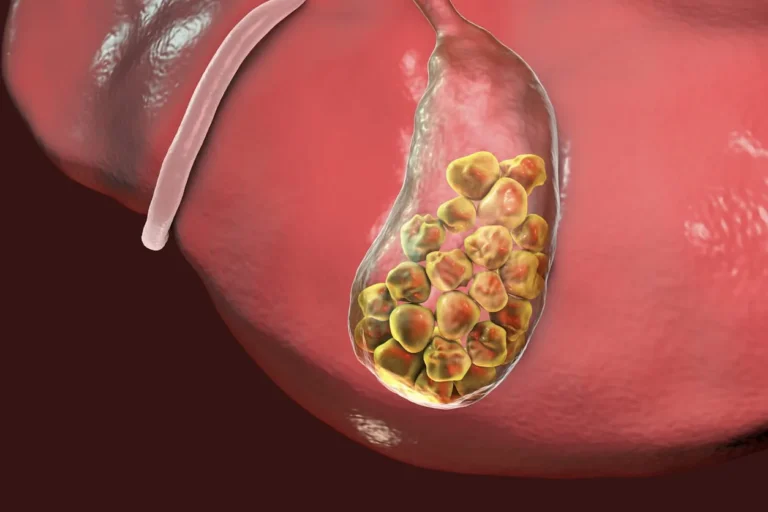

APA ITU BATU EMPEDU?

Obat Batu empedu – Batu empedu adalah gumpalan keras yang terbentuk dari endapan kolesterol atau zat sisa pencernaan di dalam kantong empedu. Kondisi ini terjadi ketika cairan empedu mengandung zat tertentu dalam kadar tinggi sehingga mengendap dan membentuk batu. Jika tidak segera ditangani, batu empedu dapat menyebabkan nyeri hebat di perut, gangguan pencernaan, hingga peradangan kantong empedu.